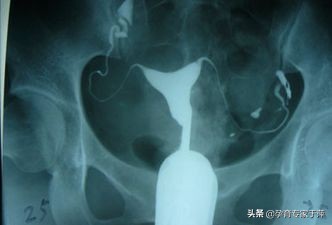

输卵管造影就是将造影剂注射到子宫腔内,造影剂可以经过输卵管进入盆腹腔内,在X线下可以清晰地看到子宫腔及两侧的输卵管的形态,是否通畅,是堵塞、黏连还是通而不畅,病灶的位置等都能清晰的看到。子宫输卵管造影术是输卵管通畅度的一线筛查手段。

1、输卵管通畅

可以看到一侧或双侧输卵管伞端有造影剂溢出,盆腔有造影剂涂抹。